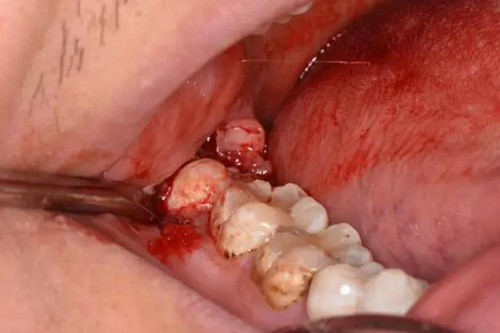

圖3.患者口內(nèi)觀:48僅萌出頰側(cè)近中一牙尖,遠(yuǎn)中有牙齦覆蓋

圖7.順著牙列長(zhǎng)軸方向、略偏頰側(cè)切開(kāi)遠(yuǎn)中齦瓣,長(zhǎng)度約1cm為宜

圖8.切開(kāi)長(zhǎng)度以暴露48遠(yuǎn)中邊遠(yuǎn)嵴為標(biāo)準(zhǔn)

圖9.翻開(kāi)覆蓋在48牙冠上方的牙齦